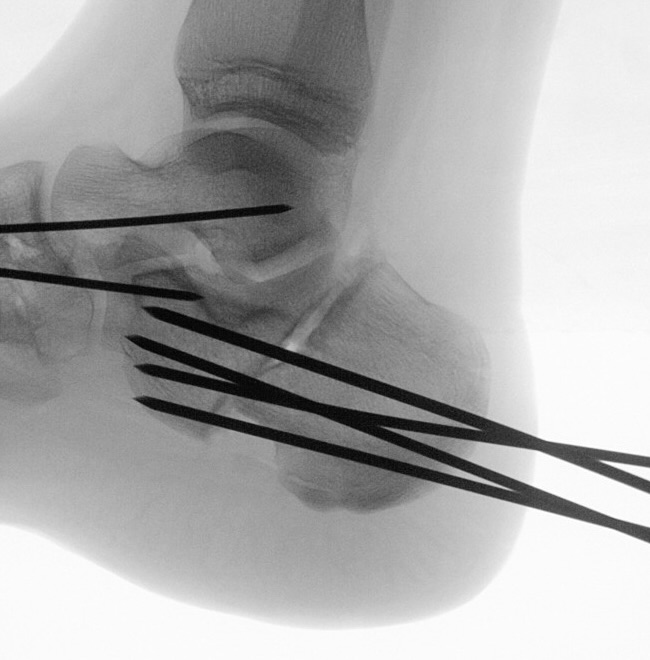

Zusätzlich schränken Wachstumsfugen die Wahl der Osteosynthese ein. Eine die Fuge kreuzende Osteosynthese ist ausschließlich mit Kirschner-Drähten möglich (Abb. 3).

Abb. 3 a-j: Beispiel einer Calcaneusverschiebeosteotomie mit offenen Wachstumsfugen und der entsprechenden Osteosynthese mit Kirschner Drähten. Lokalisation der Osteotomie (a), Lage der Fräse (b-d), Drahtlage mehrere Ansichten (e-h), Heilung der Osteotomie 4 Wochen postoperativ und Entfernung der Drähte (i-j).

Zum Lesen der Bildbeschreibung und zur Vollansicht bitte die Bilder anklicken. Bilder: A. Helmers.

Calcaneus-Osteotomie

Die minimalinvasive Calcaneusverschiebeosteotomie bietet eindeutige Vorteile gegenüber dem offenen Verfahren, sodass wir bei Kindern und Jugendlichen nahezu keine offene Verschiebeosteotomie mehr durchführen. Am Calcaneus liegt die offene Wachstumsfuge dorsal. Bei der Durchführung müssen Schenkel der V-förmigen Osteotomie daher etwas steiler angelegt werden, in einem stumpfen Winkel (siehe Abb. 3 a-j). Für die Osteotomie liegen unsere Patienten auf dem Rücken und der BV wird für die exakte Seitaufnahme eingestellt. Der Fuß lagert auf einem hohen OP-Kissen und die Osteotomie kann bequem mit einem langen Kirschner-Draht und einem sterilen Stift angezeichnet werden (Abb. 15).